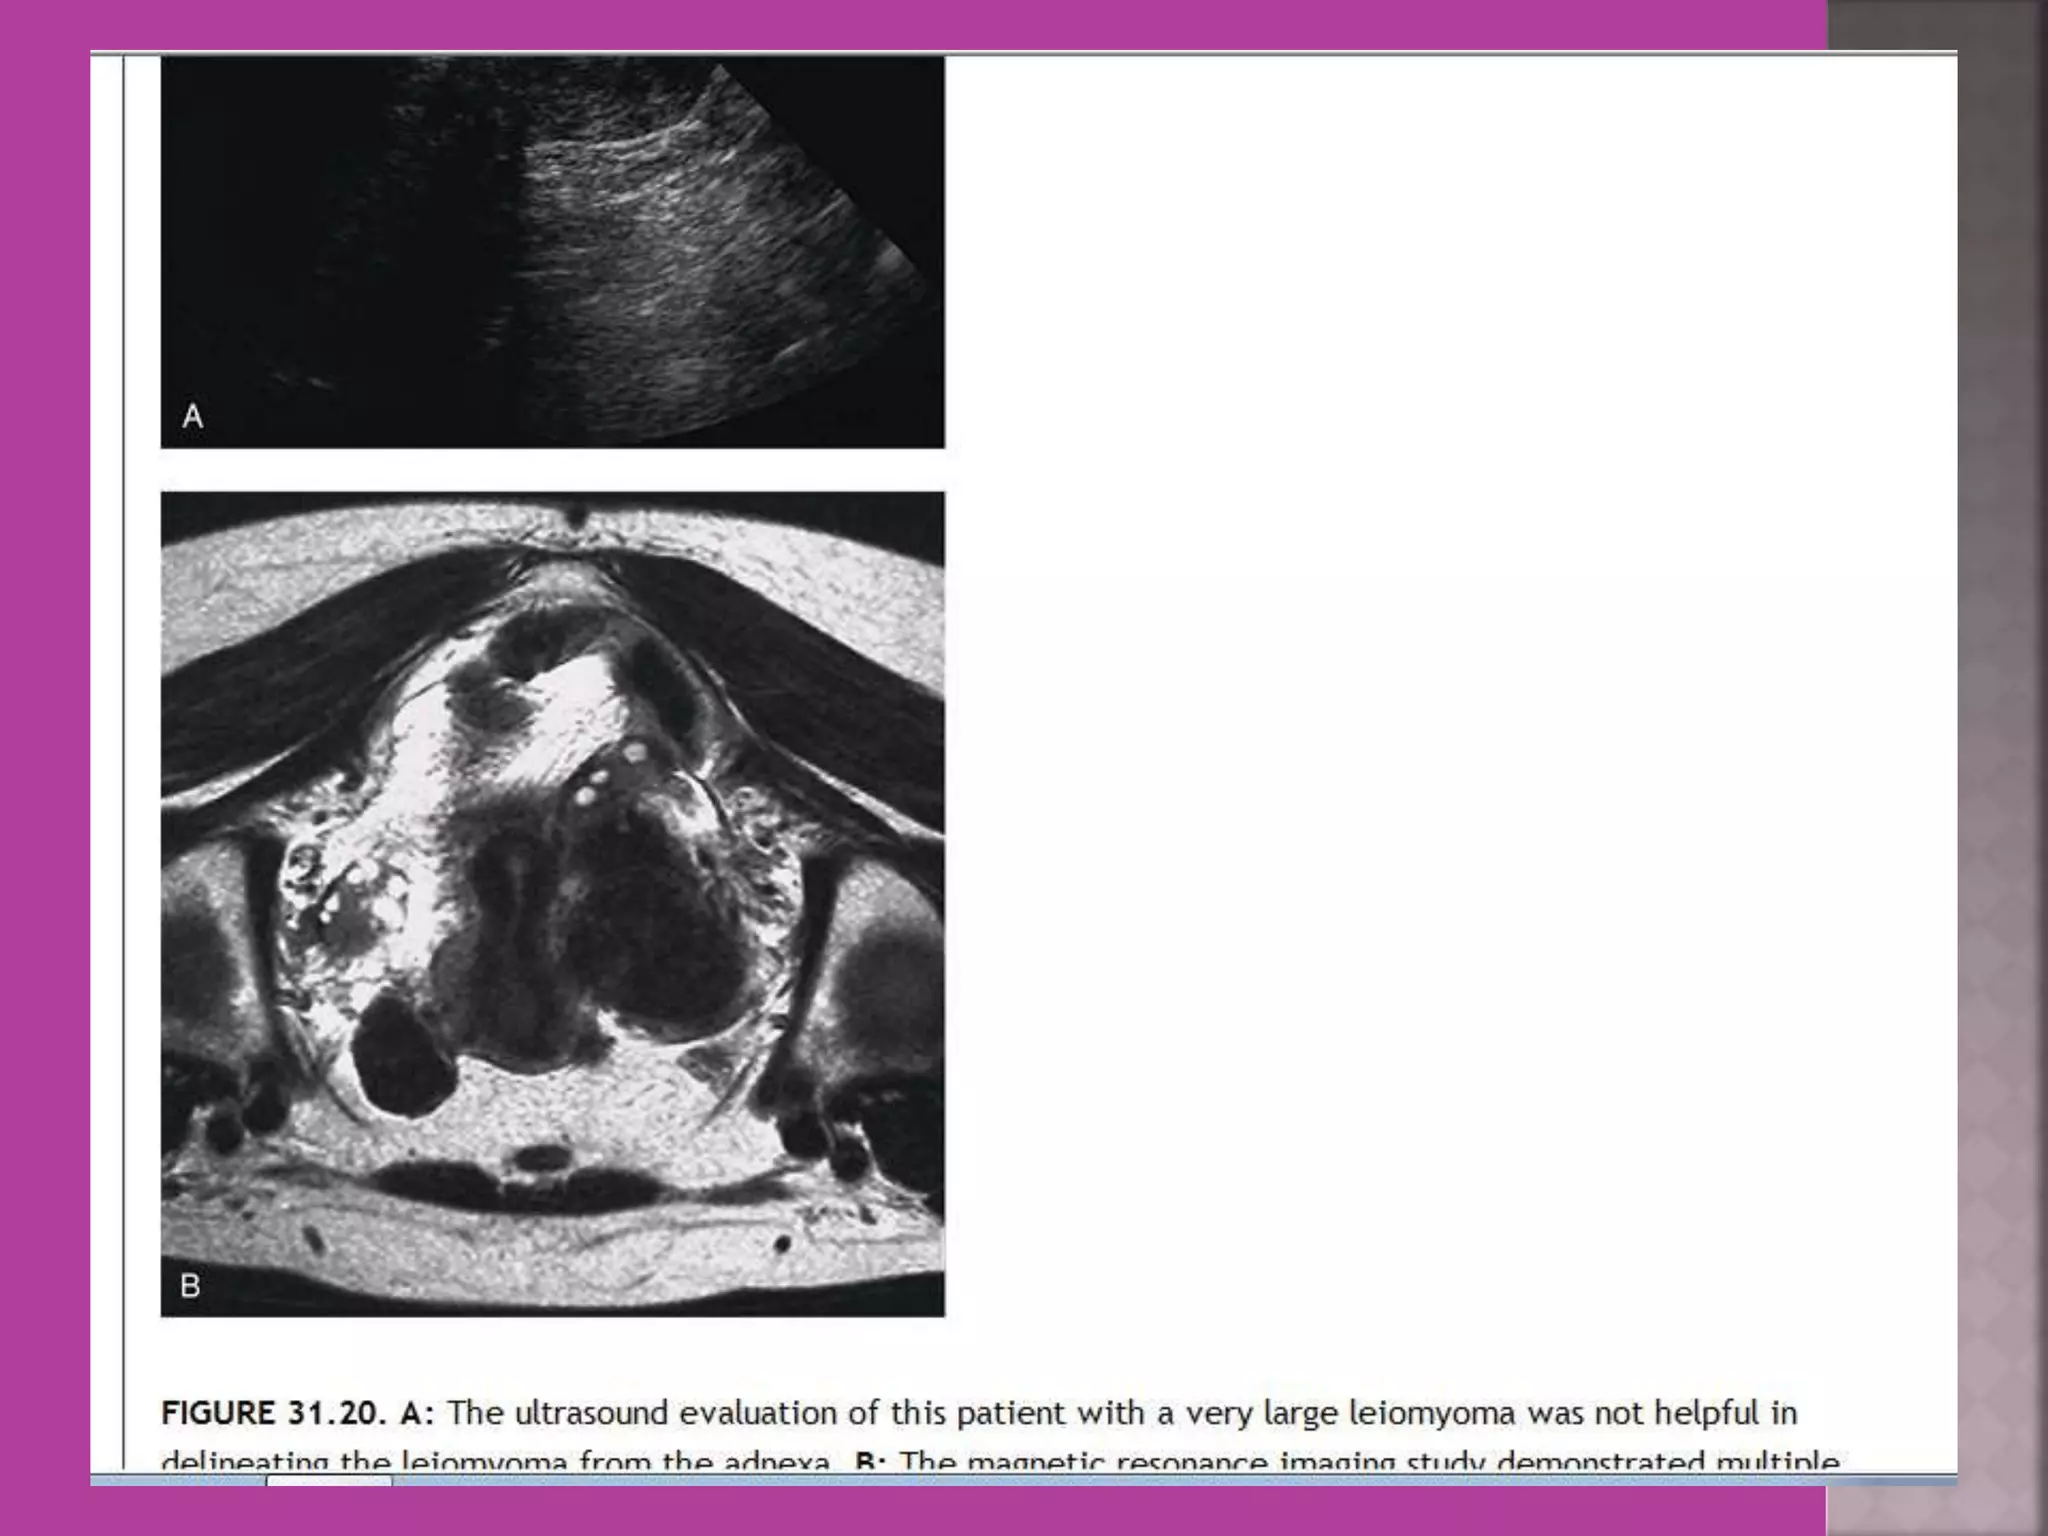

 Myoma—to differentiate myoma from

adenomyoma.localization of myoma—sub

serous/ intra mural or sub mucous.